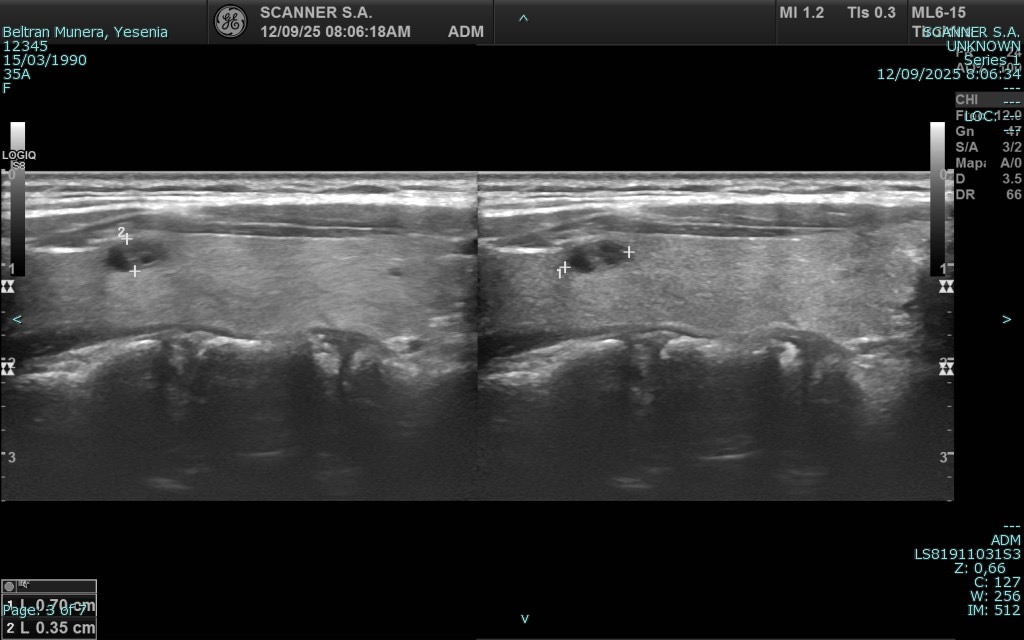

La ecografía es una técnica de diagnóstico por imagen no invasiva que utiliza ondas de ultrasonido para visualizar en tiempo real órganos, tejidos blandos y estructuras internas del cuerpo. A diferencia de otros estudios, no emplea radiación, lo que la convierte en una herramienta segura, ampliamente utilizada en diversas áreas médicas para detectar alteraciones, monitorear enfermedades y apoyar decisiones clínicas con agilidad y precisión.

En SCANNER S.A. contamos con equipos ecográficos de alta resolución, diseñados para ofrecer imágenes claras y detalladas. Nuestro servicio incluye tanto ecografía general como ecografía especializada, permitiendo realizar estudios abdominales, pélvicos, ginecológicos, obstétricos, renales, tiroideos, de partes blandas, musculoesqueléticos y más.